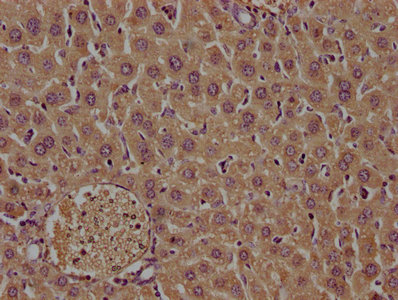

IHC image of PACO63863 diluted at 1:400 and staining in paraffin-embedded mouse liver tissue performed on a Leica BondTM system. After dewaxing and hydration, antigen retrieval was mediated by high pressure in a citrate buffer (pH 6.0). Section was blocked with 10% normal goat serum 30min at RT. Then primary antibody (1% BSA) was incubated at 4°C overnight. The primary is detected by a biotinylated secondary antibody and visualized using an HRP conjugated SP system.